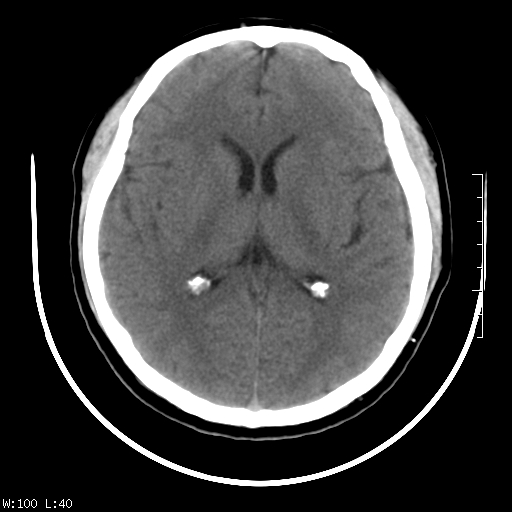

标题: CT22236:男,45,经常头痛。看看脑干正常吗? [打印本页]

标题: CT22236:男,45,经常头痛。看看脑干正常吗?

未见明显异常,建议ct增强或mri检查。

没见异常密度及形态改变啊,我认为是正常的。

颅脑ct轴位平扫颅内未见明确异常。

颅脑ct平扫未见明确异常,必要时mri检查。

颅脑ct平扫未见异常